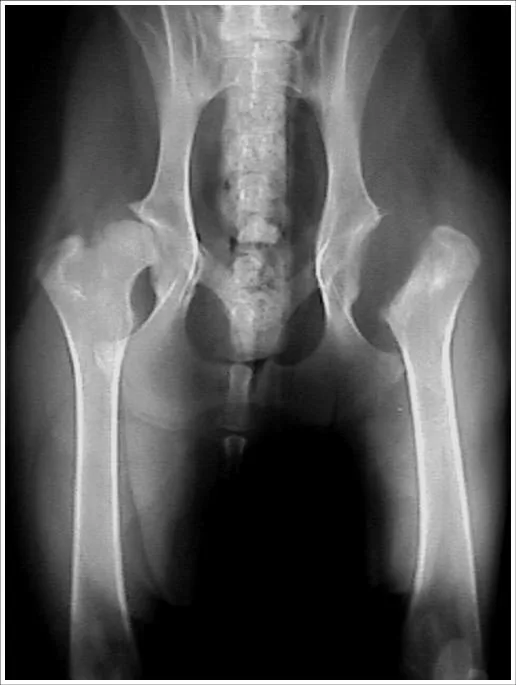

The animal should be routinely anesthetized using a premedication, an induction agent, and gas anesthesia; then placed in lateral recumbency with the affected limb hung and aseptically prepared for surgery (A).

The hip is then draped routinely to allow manipulation of the limb. A proper craniolateral approach to the hip is dependent on the identification of the ischial tuberosity (white arrow), the greater trochanter (arrowhead), and iliac wing of the pelvis (red arrow) (B).